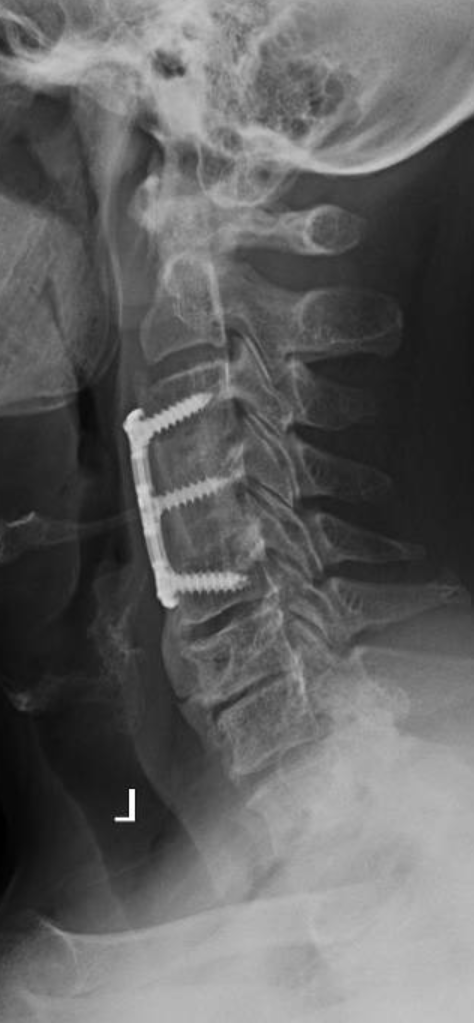

I performed a partial C4 corpectomy with fibular allograft -Abscesses can be more solid than expected -Partial corpectomy offers excellent decompression + stability -Material choice (titanium/allograft/autograft) matters less than thorough I&D and stabilization #cervicalspine

What would your surgical plan be for this patient with a cervical epidural abscess and severe arm weakness? #neurosurgery #physicaltherapy #chiropractor #spine #spinehealth #spinesurgery #cervicalspine